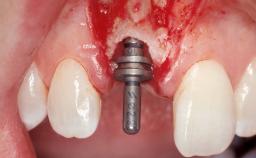

A 42-year-old female patient was referred to our clinic at the School of Dentistry of the University of São Paulo in November 2004, presenting a deficient restoration in the upper left central incisor. The clinical examination revealed no gingival retraction or any signs of gingival inflammation and, therefore, previous periodontal treatment was not considered. The patient presented a high lip line at full smile and a thin tissue biotype. This combination characterized a high-risk situation from an anatomic point of view, which required careful preoperative planning and cautious surgical execution.

Placement Protocol Immediate implant placement

Tooth Site Maxillary incisor or canine

Socket Morphology Single-root socket

Socket Integrity Sufficient, with intact bone walls

Loading Protocol Immediate